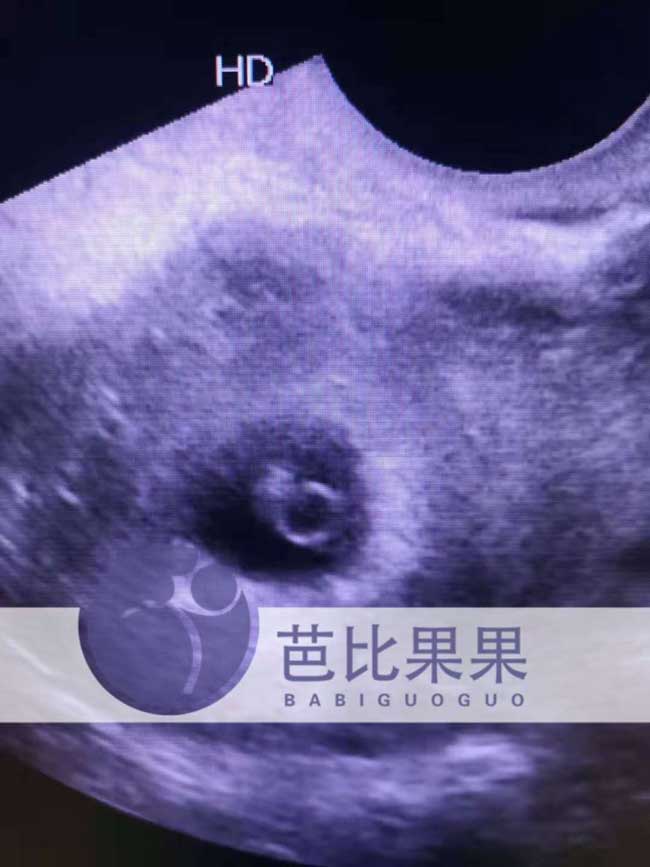

H女士的乌克兰试管做了第一次B超,官宣有喜啦,胎心胎芽顺利过关,希望一切如意,明年顺利抱上牛宝宝